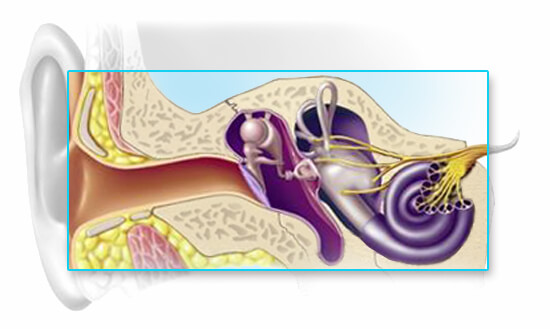

Mixed Hearing Loss

A mixed hearing loss can be thought of as a sensorineural hearing loss with a conductive component overlaying all or part of the audiometric range tested. So, in addition to some irreversible hearing loss caused by an inner ear or auditory nerve disorder, there is also a dysfunction of the middle ear mechanism that makes the hearing worse than the sensorineural loss alone.

The conductive component may be amenable to medical treatment and reversal of the associated hearing loss, but the sensorineural component will most likely be permanent. Hearing aids can be beneficial for individuals with a mixed hearing loss, but caution must be exercised by the hearing care professional if the conductive component is due to an active ear infection.